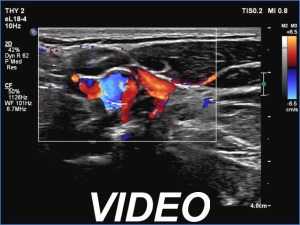

The differentiation of a lymph node from a discrete thickening of a muscle fiber can be challenging. If the node in this case would be non-palpable then it would be almost impossible to make this distinction. The echo patterns are identical and hilum-like adipose tissue is a common finding in muscle fibers. The only important ultrasound feature is the presence of vascularity according to the hilum. This was not demonstrated on color Doppler mode but was on microflow imaging.